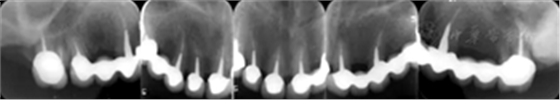

3.影像學檢查:

全口根尖X線片示鄰面骨嵴頂影像模糊;根管欠填、根充不致密,、未見根管治療影像,、根尖周可見低密度影像(圖2)。

圖2 患者初診時全口根尖X線片